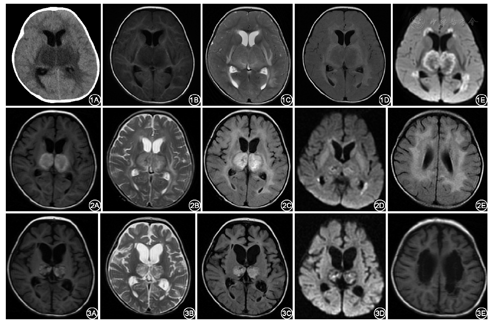

(1)CT和MRI:ANE的初期影像改变:病变部位主要表现为脑水肿,病灶在脑头颅CT上(图1)表现为低密度信号。头颅MRI(图1)病灶为长T1长T2,液体衰减反转恢复(Flair)和弥散加权成像(DWI)为高信号,灰质病灶可以为同心圆样的混杂信号。

ANE的中期影像改变:病变主要表现为点状出血、坏死。在头颅CT上表现杂色,为花斑状低密度区中掺杂不规则高密度影,脑白质密度更低。头颅MRI(图2):灰质病灶(主要是丘脑)在T1、T2、Flair、DWI均可见同心圆样环状表现。T1:中心低信号,周围环状高信号为亚急性出血改变;T2:之前的高信号有所减低,周围环绕高信号或等信号,小点状出血在T2通常是模糊的。Flair:高信号更加明显,中心及外周均混杂有低信号。DWI:混杂信号,高信号较前减少。脑白质始终是长T1长T2,Flair高信号。

ANE的恢复期影像改变:少数轻型病例病灶可完全消失,大部分病例病灶表现为萎缩、含铁血黄素沉积、囊腔形成等退行性改变,在头颅CT及MRI均会留下囊腔形成或大脑萎缩等异常信号,部分病例亚急性出血囊腔形成等异常信号持续存在数月至数年,MRI表现见图3。

经典ANE神经影像特点(图4)为"同心圆、三色板模式或靶样形状",这种典型改变因为没有T2穿透效应的限制,在头颅MRI的表观弥散系数(ADC)图上尤为明显。病变中央部显示为略高信号,周围病变为低信号(表示细胞毒性水肿),损害灶的外围部有比中央更高的信号(表示血管源性水肿)。ANE的病理改变可解释上诉神经影像学改变。通常,病变的中心是血管周围出血、神经元坏死和神经胶质细胞增生,ADC显示略高信号;在中心的外围部分显示低信号,为动脉、静脉及毛细血管淤血和少突胶质细胞急性水肿;最外层的高信号为病变的渗出,即血管源性水肿。值得注意的是典型的病变主要出现在灰质,特别是在双侧丘脑。